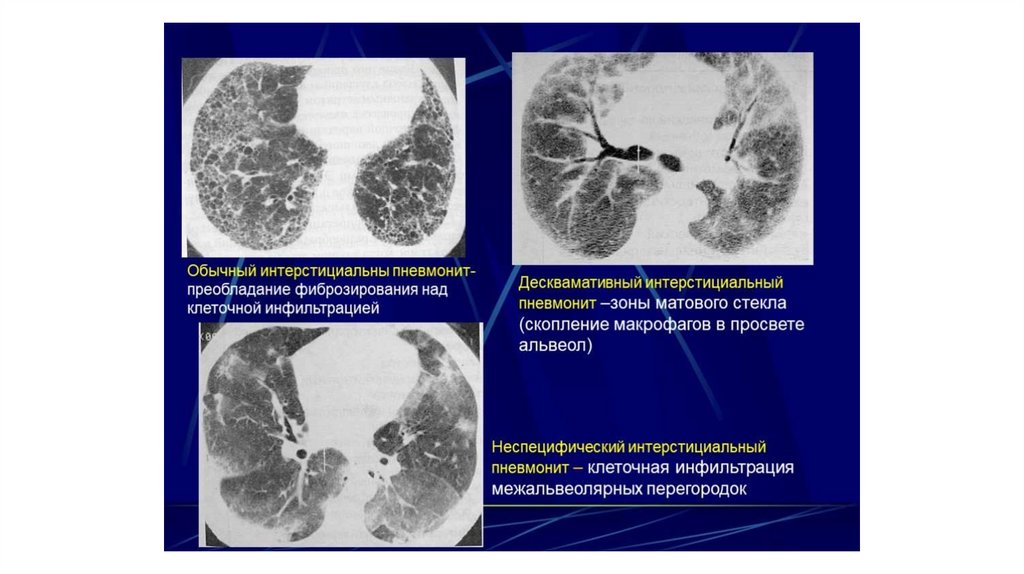

Морфологическая картина НСИП отличается гомогенностью

изменений. При НСИП в данное время присутствует

воспаление или фиброз примерно на одном этапе развития.

Морфологические изменения носят диффузный характер.

По морфологической картине НСИП можно разделить на три группы:

1) клеточный вариант - с преобладанием картины воспаления;

2) фибротический вариант - с преобладанием паттерна фиброза;

3) смешанный вариант, при котором одновременно присутствуют и

воспаление, и фиброз.

При рентгенографии грудной клетки при НСИП чаще всего

выявляются двусторонние изменения по типу «матового

стекла» и ретикулярные изменения в нижних отделах лёгких.

Характерным признаком НСИП при компьютерной томографии

высокого разрешения является симптом «матового стекла»,

часто в сочетании с признаками лёгочного фиброза

(уменьшение объёма лёгких, ретикулярные изменения,

тракционные бронхоэктазы). Типичная картина КТВР при НСИП

включает смешанный паттерн «матового стекла» и

консолидации (в случае выраженного клеточного

воспаления), а также иррегулярные линии с типичным

периферическим, субплевральным, базальным

симметричным распространением (при фибротическом

варианте).